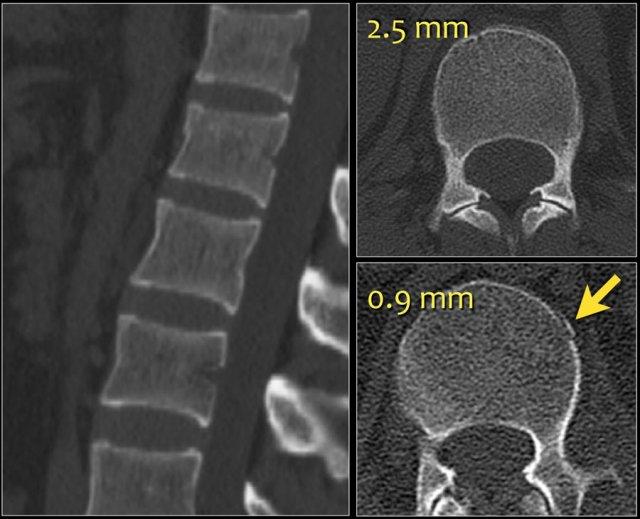

Các hình ảnh cho thấy một trường hợp gãy xương nén.

Dấu hiệu duy nhất quan sát được là sự gián đoạn vỏ xương ở thành trước trên của thân đốt sống và mất chiều cao nhẹ ở phía trước.

Vỏ xương phía sau thân đốt sống còn nguyên vẹn.

Hình tái tạo mặt phẳng đứng dọc cũng cho thấy sự gián đoạn vỏ xương.

Lưu ý rằng trên lát cắt axial dày 2,5mm, có thể bỏ sót các gãy xương này.

Cần xem xét các lát cắt mỏng để phát hiện những gãy xương tinh tế như vậy.